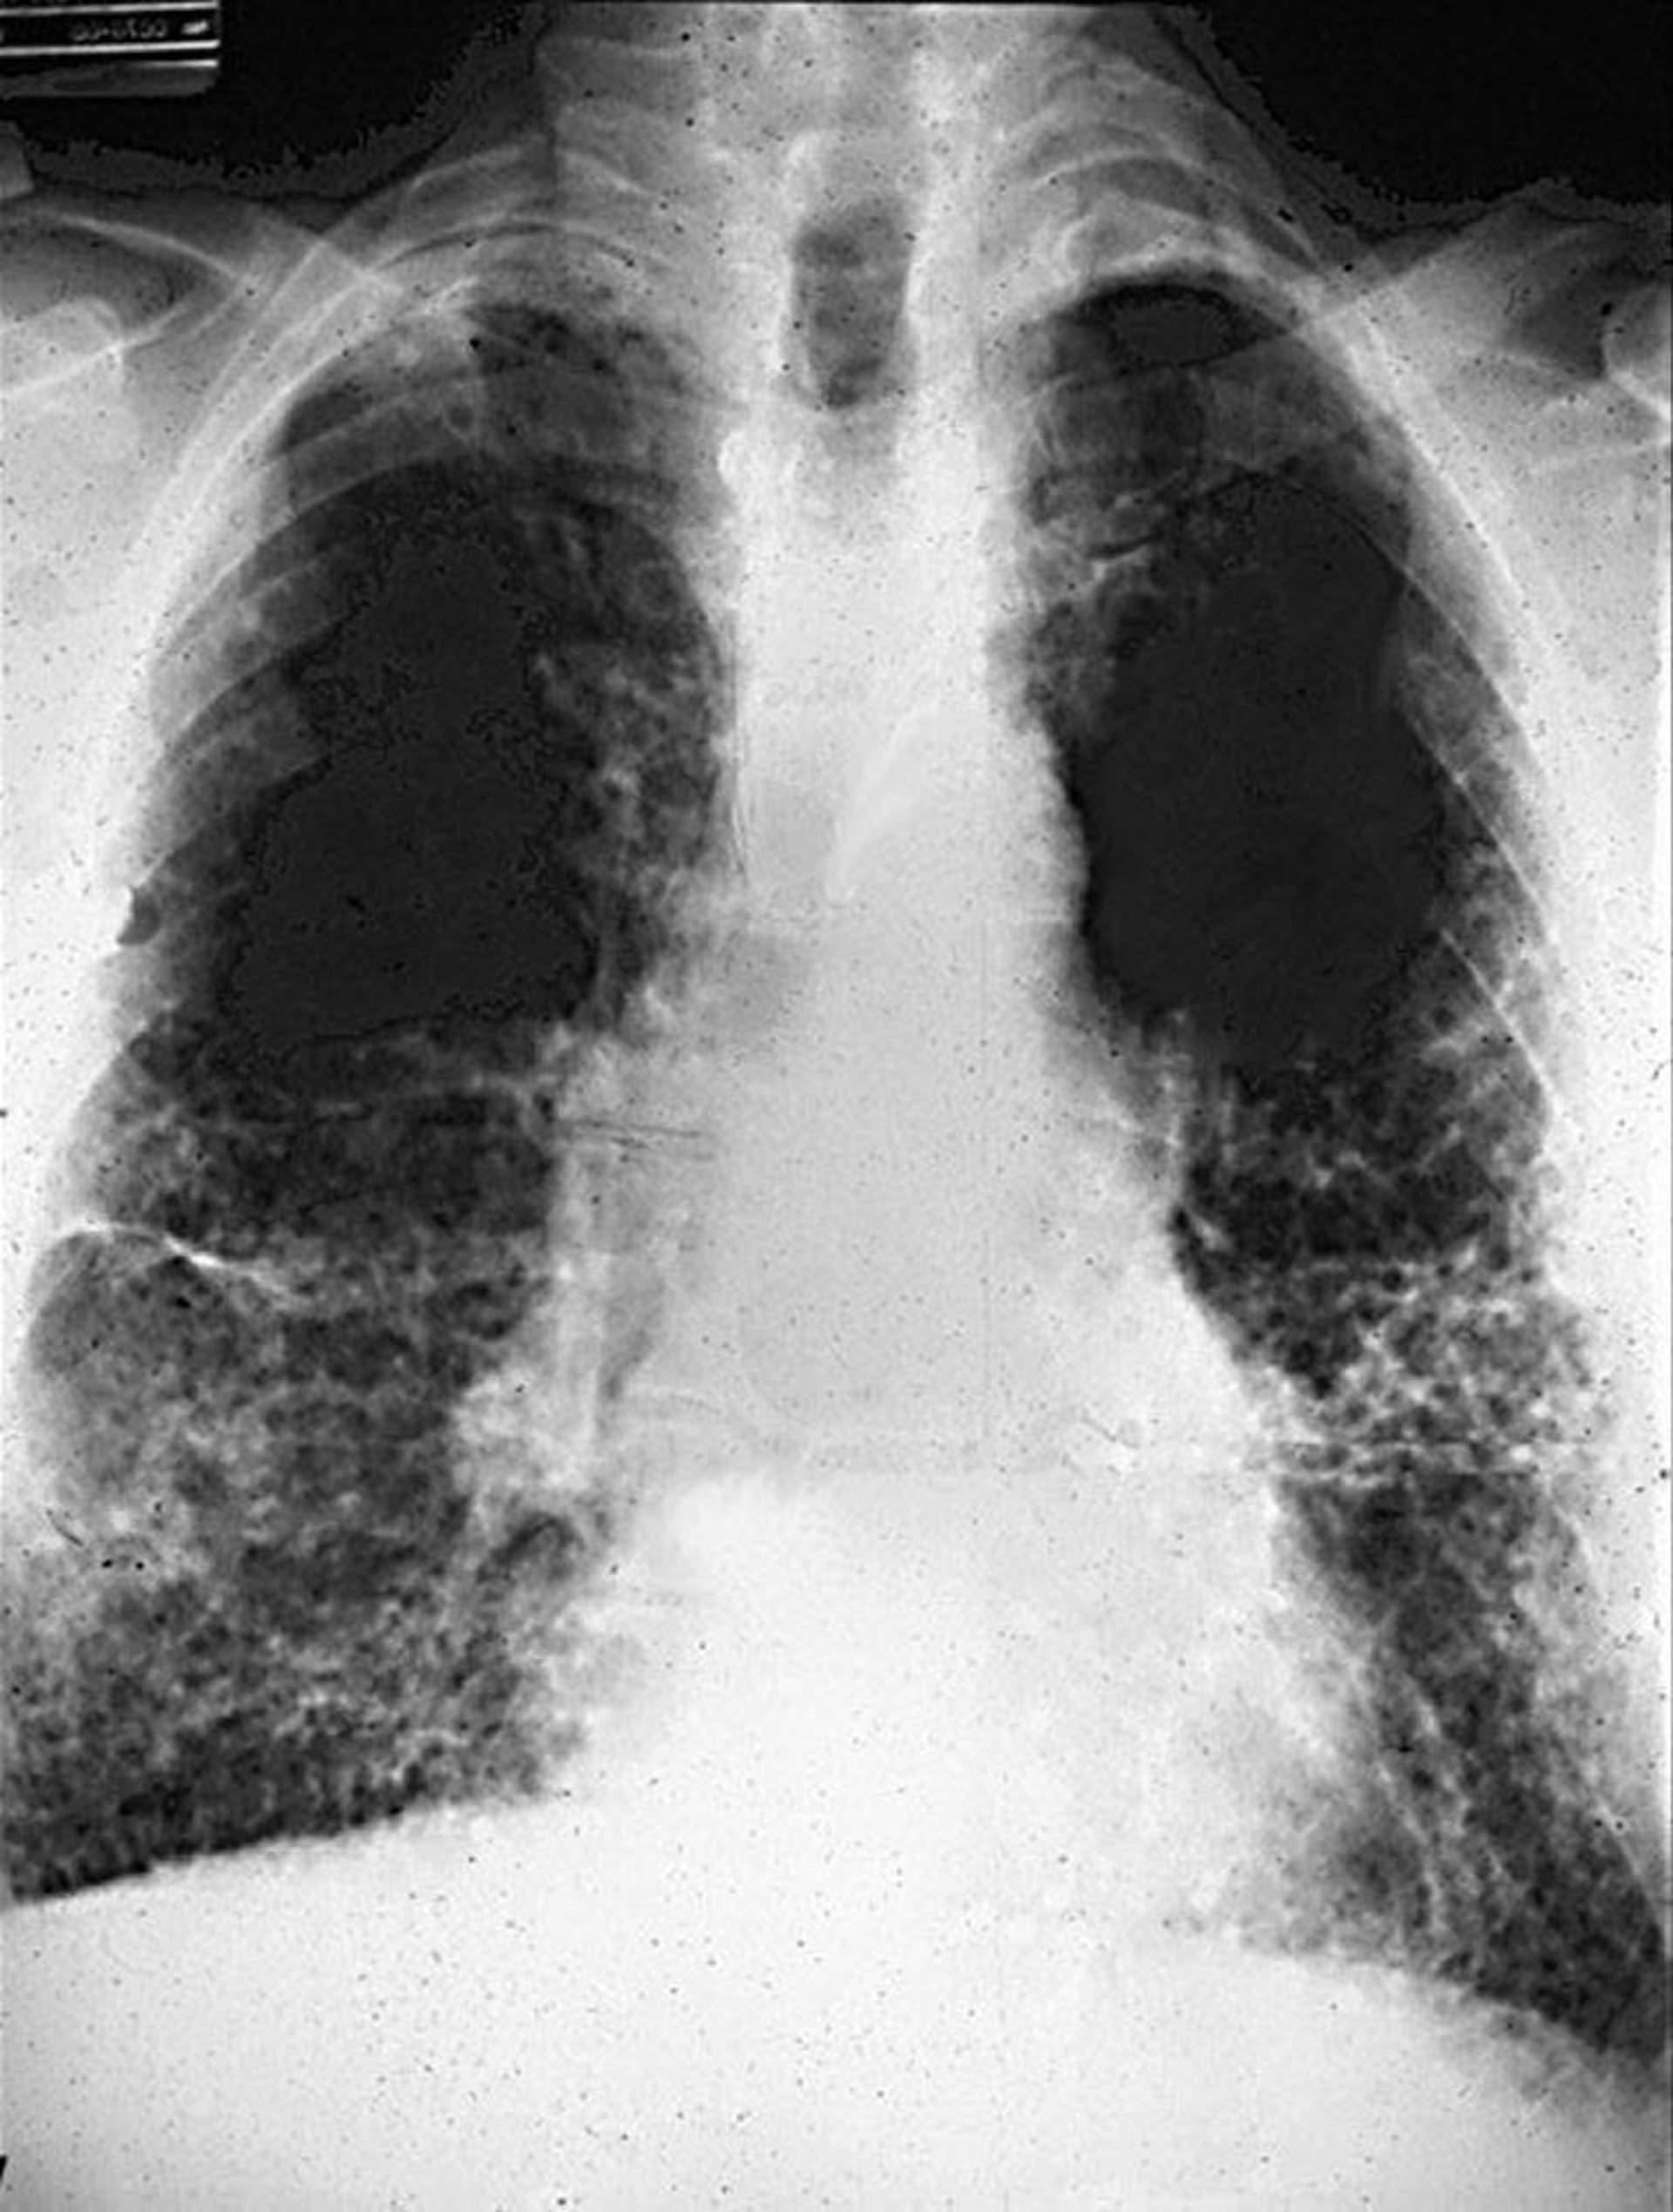

Chụp X-quang ngực cho thấy các đám mờ dạng lưới tuyến tính hai bên biểu thị tình trạng xơ hóa, thường ở ngoại vi thùy dưới, có hoặc không có thay đổi ở màng phổi. CT ngực có độ nhạy cao hơn trong việc xác định các bất thường ở màng phổi và nhu mô, và thường cho thấy dạng viêm phổi kẽ thông thường của xơ phổi. Tổ ong, có thể liên quan đến vùng giữa và vùng dưới phổi, biểu thị bệnh đã tiến triển hơn.

Hệ thống Tổ chức Lao động Quốc tế (Phân loại quốc tế về X quang phổi) được sử dụng để mô tả sự hiện diện và mức độ nặng của bệnh bụi phổi dựa trên kích thước, hình dạng, vị trí và mức độ mờ đục. Bệnh bụi phổi amiăng tạo ra các đám mờ dạng lưới với ưu thế ở thùy dưới. Rốn phổi và trung thất rộng và nốt mờ thì không đặc trưng cho bệnh và gợi ý chẩn đoán khác.

Hình ảnh do bác sĩ David W. Cugell cung cấp